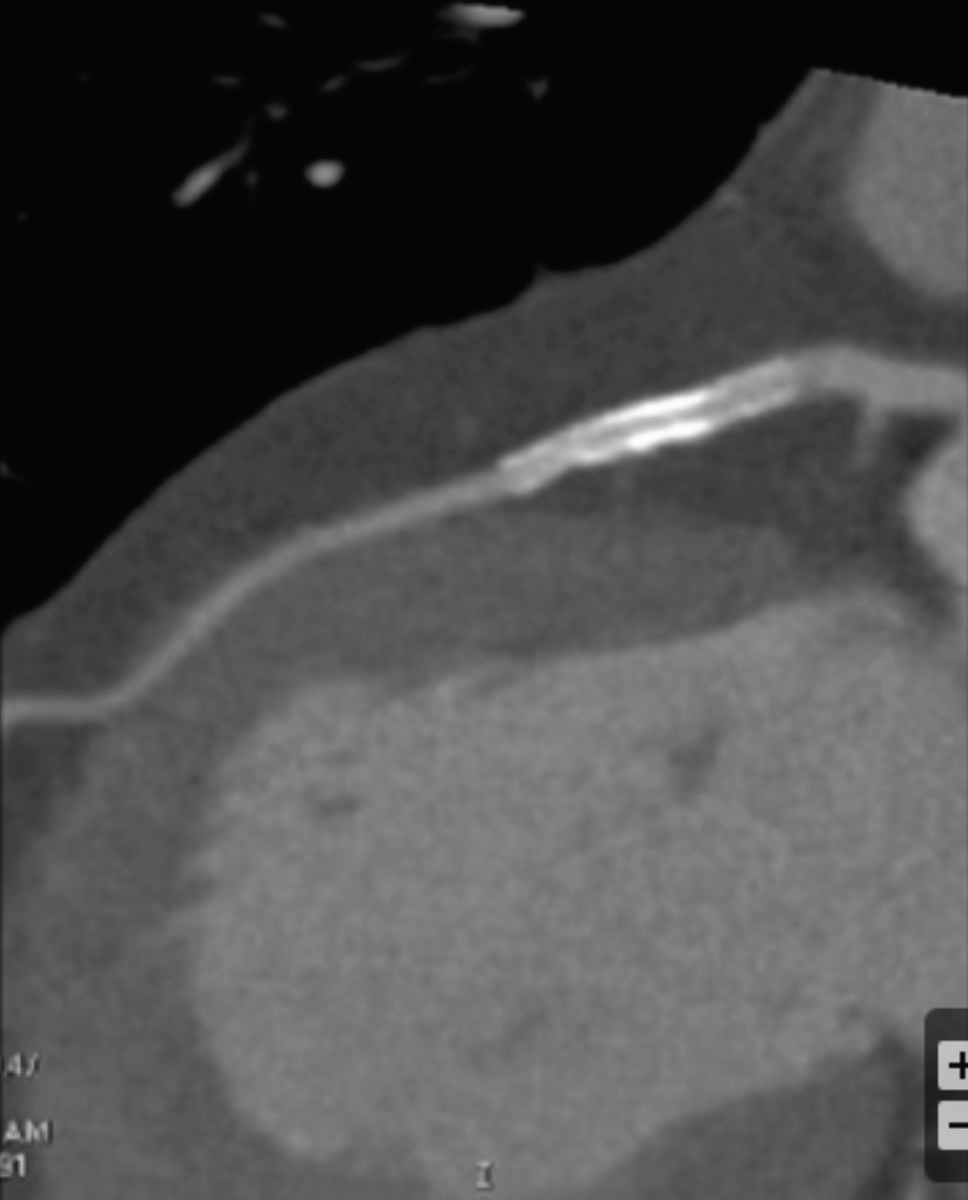

What can be done to improve visualization of the proximal LAD?

Increase Peak Tube Voltage